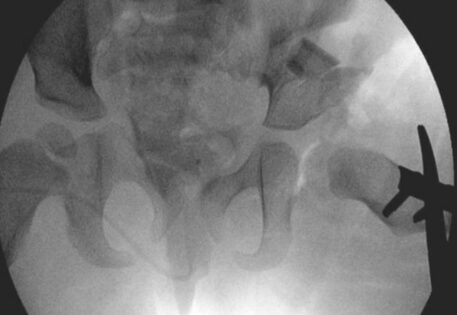

Dr. Qureshi has successfully managed numerous cases of syndromic hip dysplasia, employing investigations such as arthrography and CT imaging to assess reconstruction feasibility and plan surgical interventions. The treatment strategy is customarily crafted as a tailored combination of different techniques to address distinct components and contributory factors contributing to the dislocation.